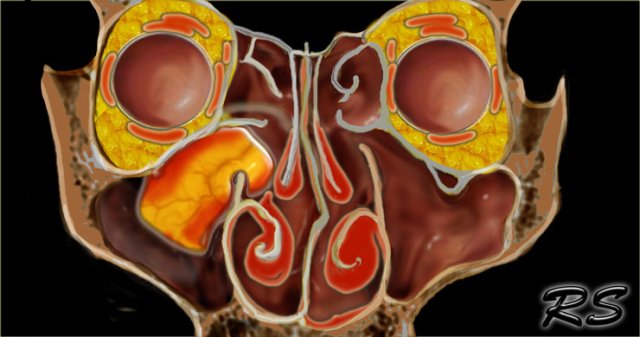

Left is an axial T1WI, right is a coronal T2WI.

The yellow arrows point to the naso-lacrimal ducts.

The naso-lacrimal sac connects with the duct, which then drains into the inferior meatus.

On the left there is peri-orbital pre-septal soft tissue swelling.

On the coronal image there is bilateral high signal at the junction of the nasolacrimal duct and sac, indicative of a fluid collection.

On the left side there is also edema of the surrounding tissue.

This patient had acute sinusitis which was complicated by orbital cellulitis and dacrocystitis with abscesses.

Developmental or inflammatory narrowing of the naso-lacrimal duct is a risk factor for developing dacrocystitis.